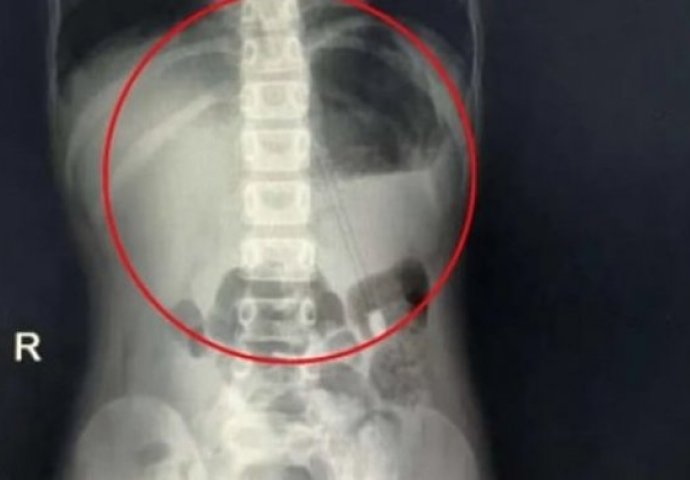

Rendgenski snimci pokazali su šiljati objekat duž djetetovog abdomena.

„Imao je sreće jer je oštar dio olovke bio na gornjoj strani. Da je bio okrenut nadole, verovatno bi mu olovka probušila želudac i druge dijelove digestivnog trakta“, objasnio je šef lekarskog tima koji je u bolnici u Henanu bio zadužen za dječaka.